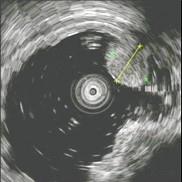

问题 男性,60岁。胃溃疡病史8年,近3月腹痛、腹胀、食欲减退、消瘦明显、粪隐血持续阳性,应用抗酸剂治疗胃痛无效。胃镜检查如图:该病人最可能的诊断是 ( )

选项 A、胃泌素瘤 B、胃溃疡恶变 C、穿透性胃溃疡 D、顽固性溃疡 E、复合溃疡

答案 B